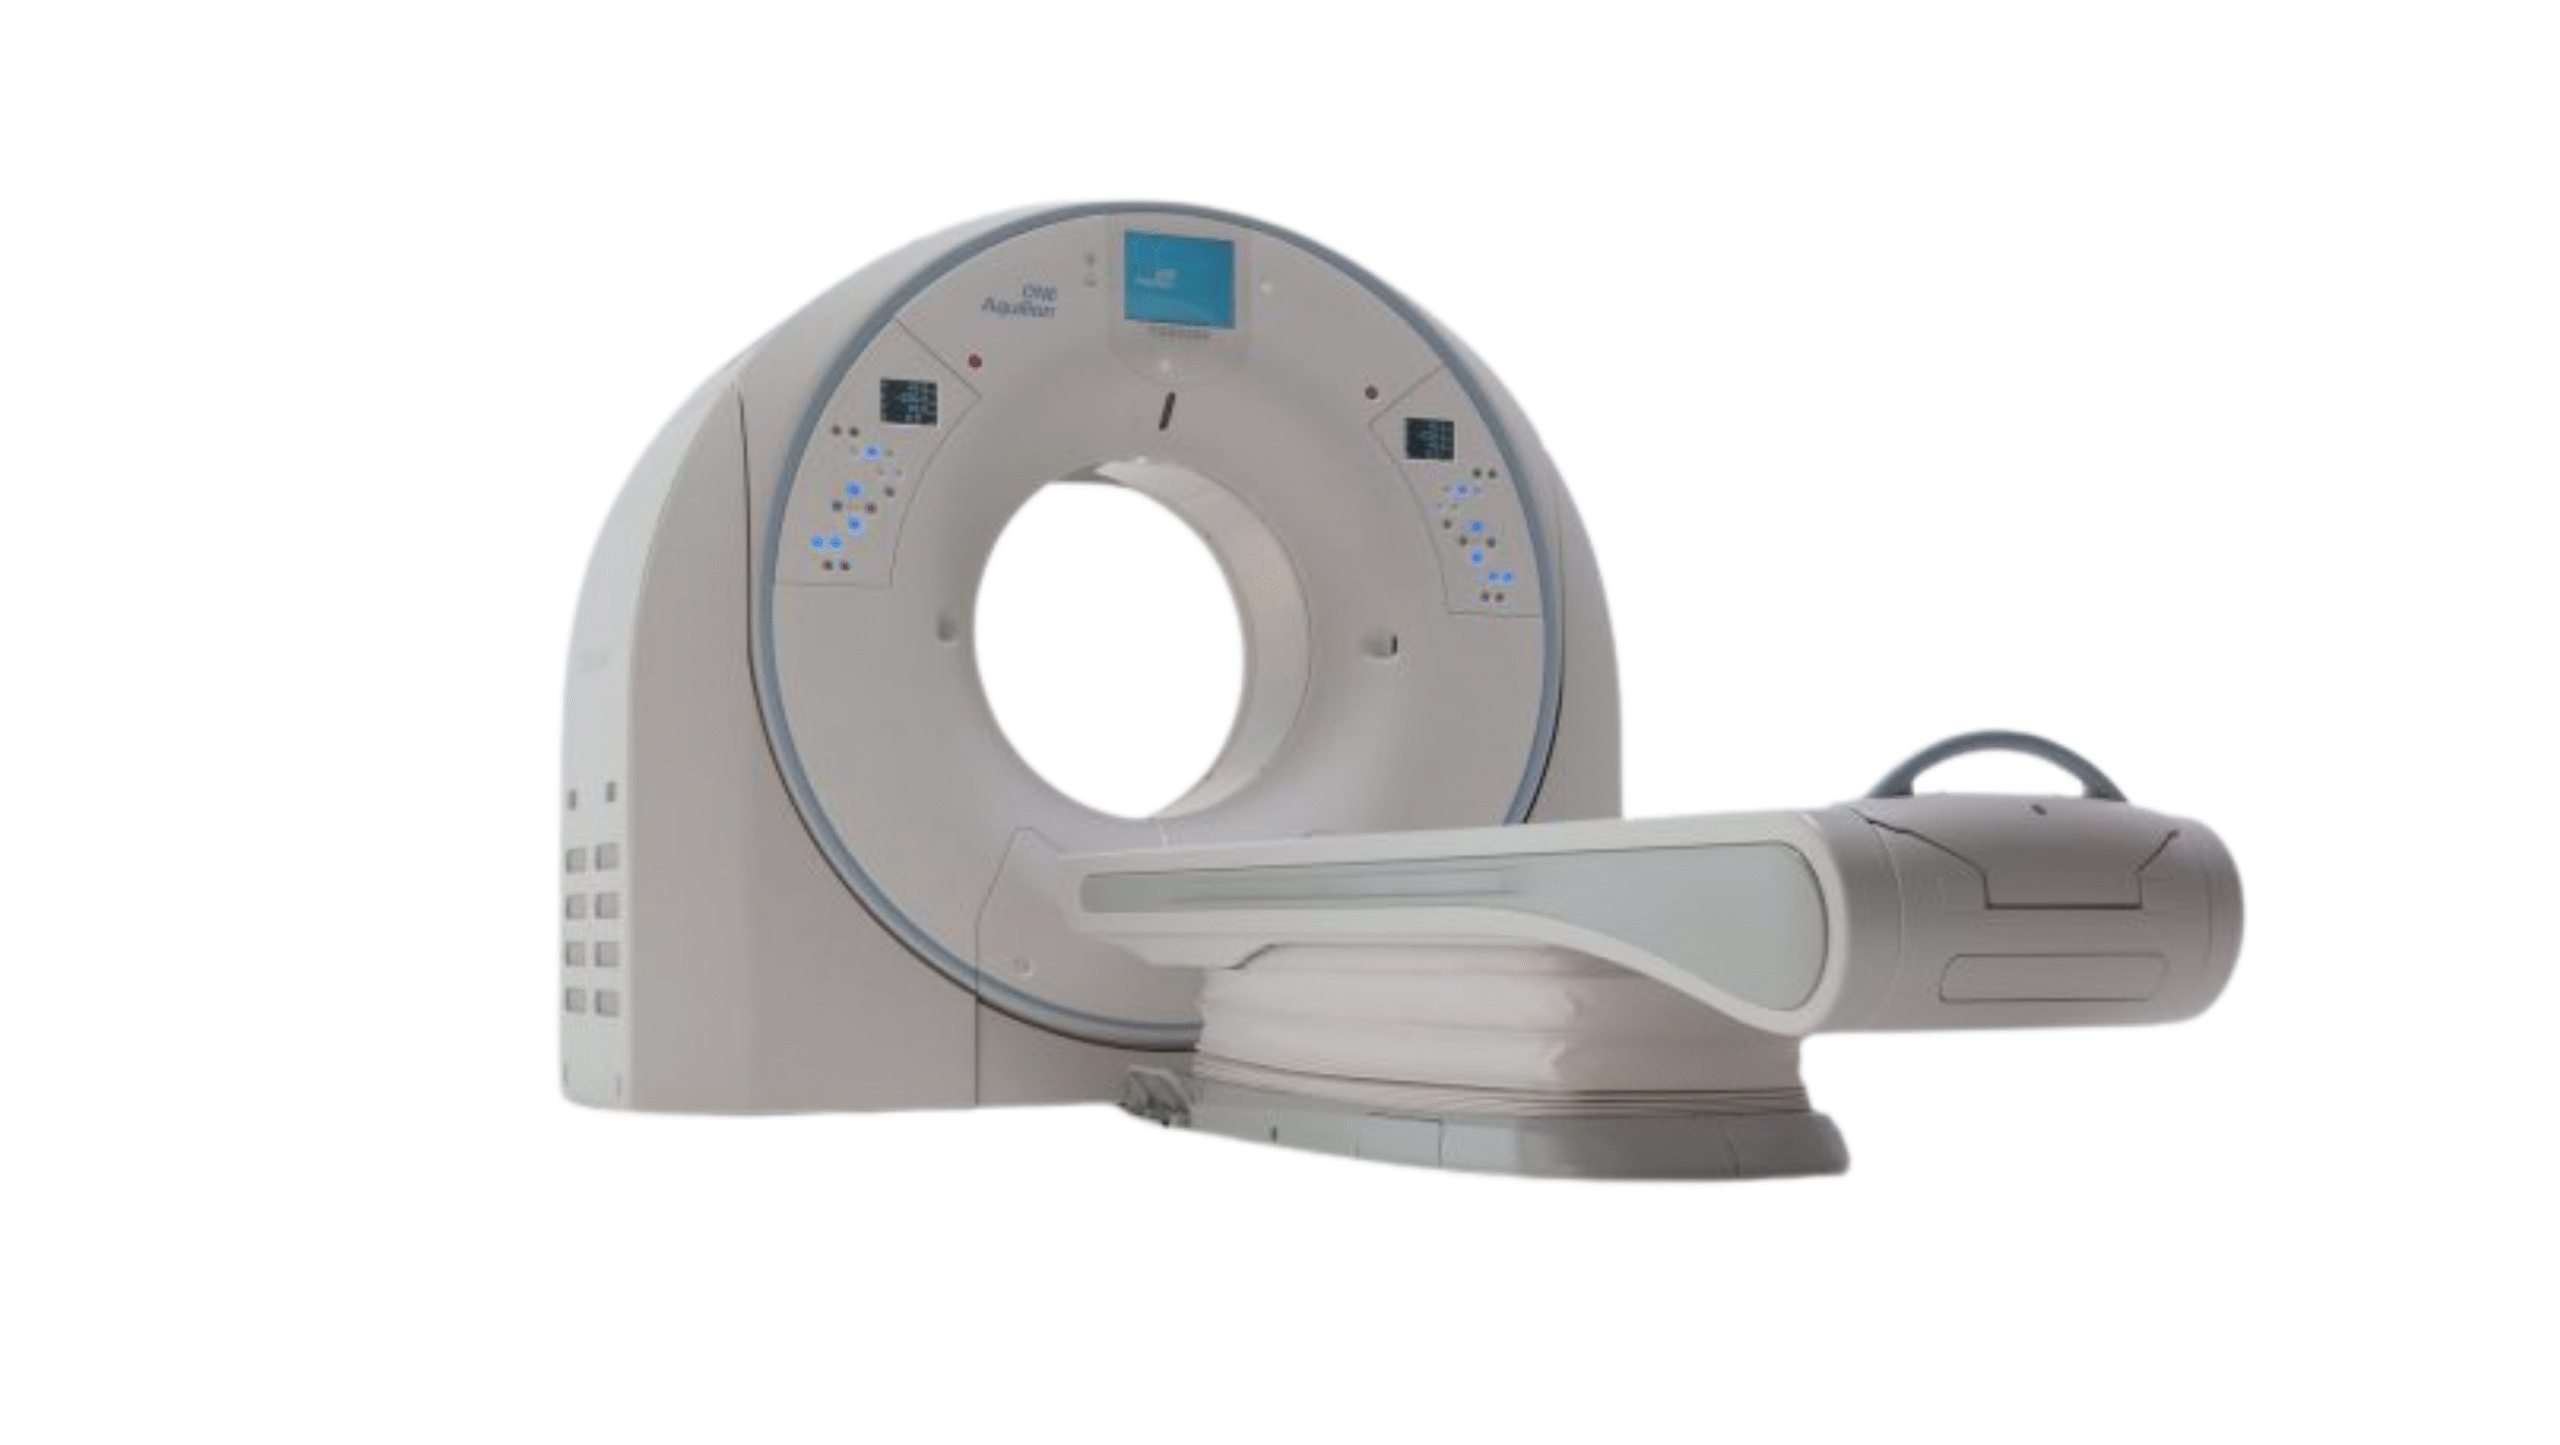

Products

We provide reliable service for our partners all around the globe. Offering well-known brands such as Fujifilm Healthcare, Carestream Health, Konica Minolta Healthcare and many others. Minimum order quantity is 1 pallet.